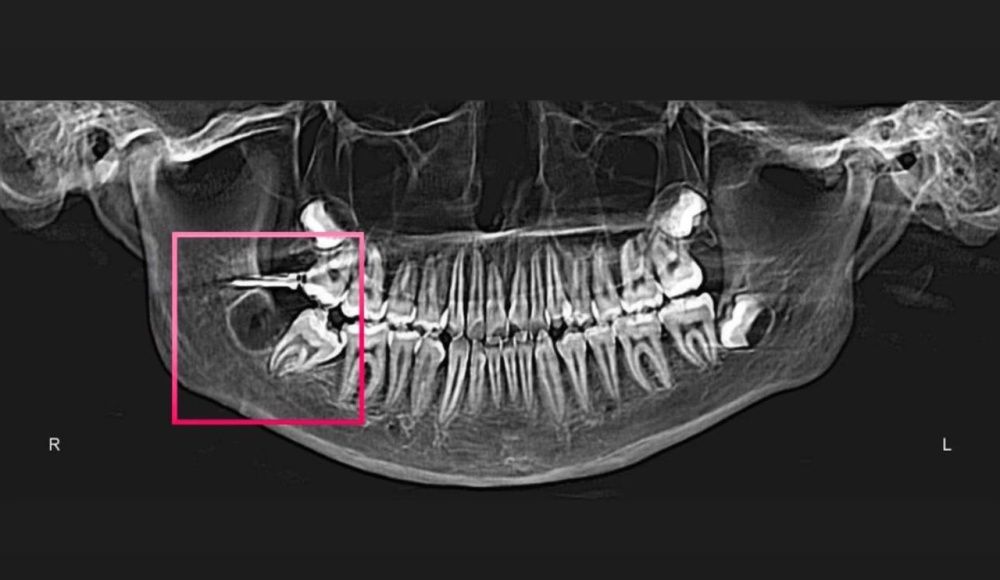

При проведении компьютерной томографии челюстей выявлено полуретенция (неправильное прорезывание) жевательного зуба 4.7, и зачаток зуба мудрости 4.8, который будет препятствовать дальнейшему лечению.